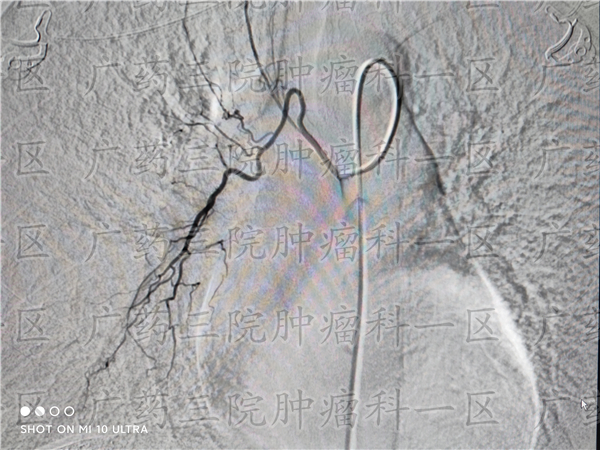

但如果患者的治疗效果比较一般,或者在后期的内分泌治疗中,癌细胞没有得到控制,发生了转移,那么患者的治疗就需要再次启动。一般来说,对乳腺癌患者,广东药科大学广州复星禅诚医院肿瘤科一区医生建议患者进行全程管理治疗。